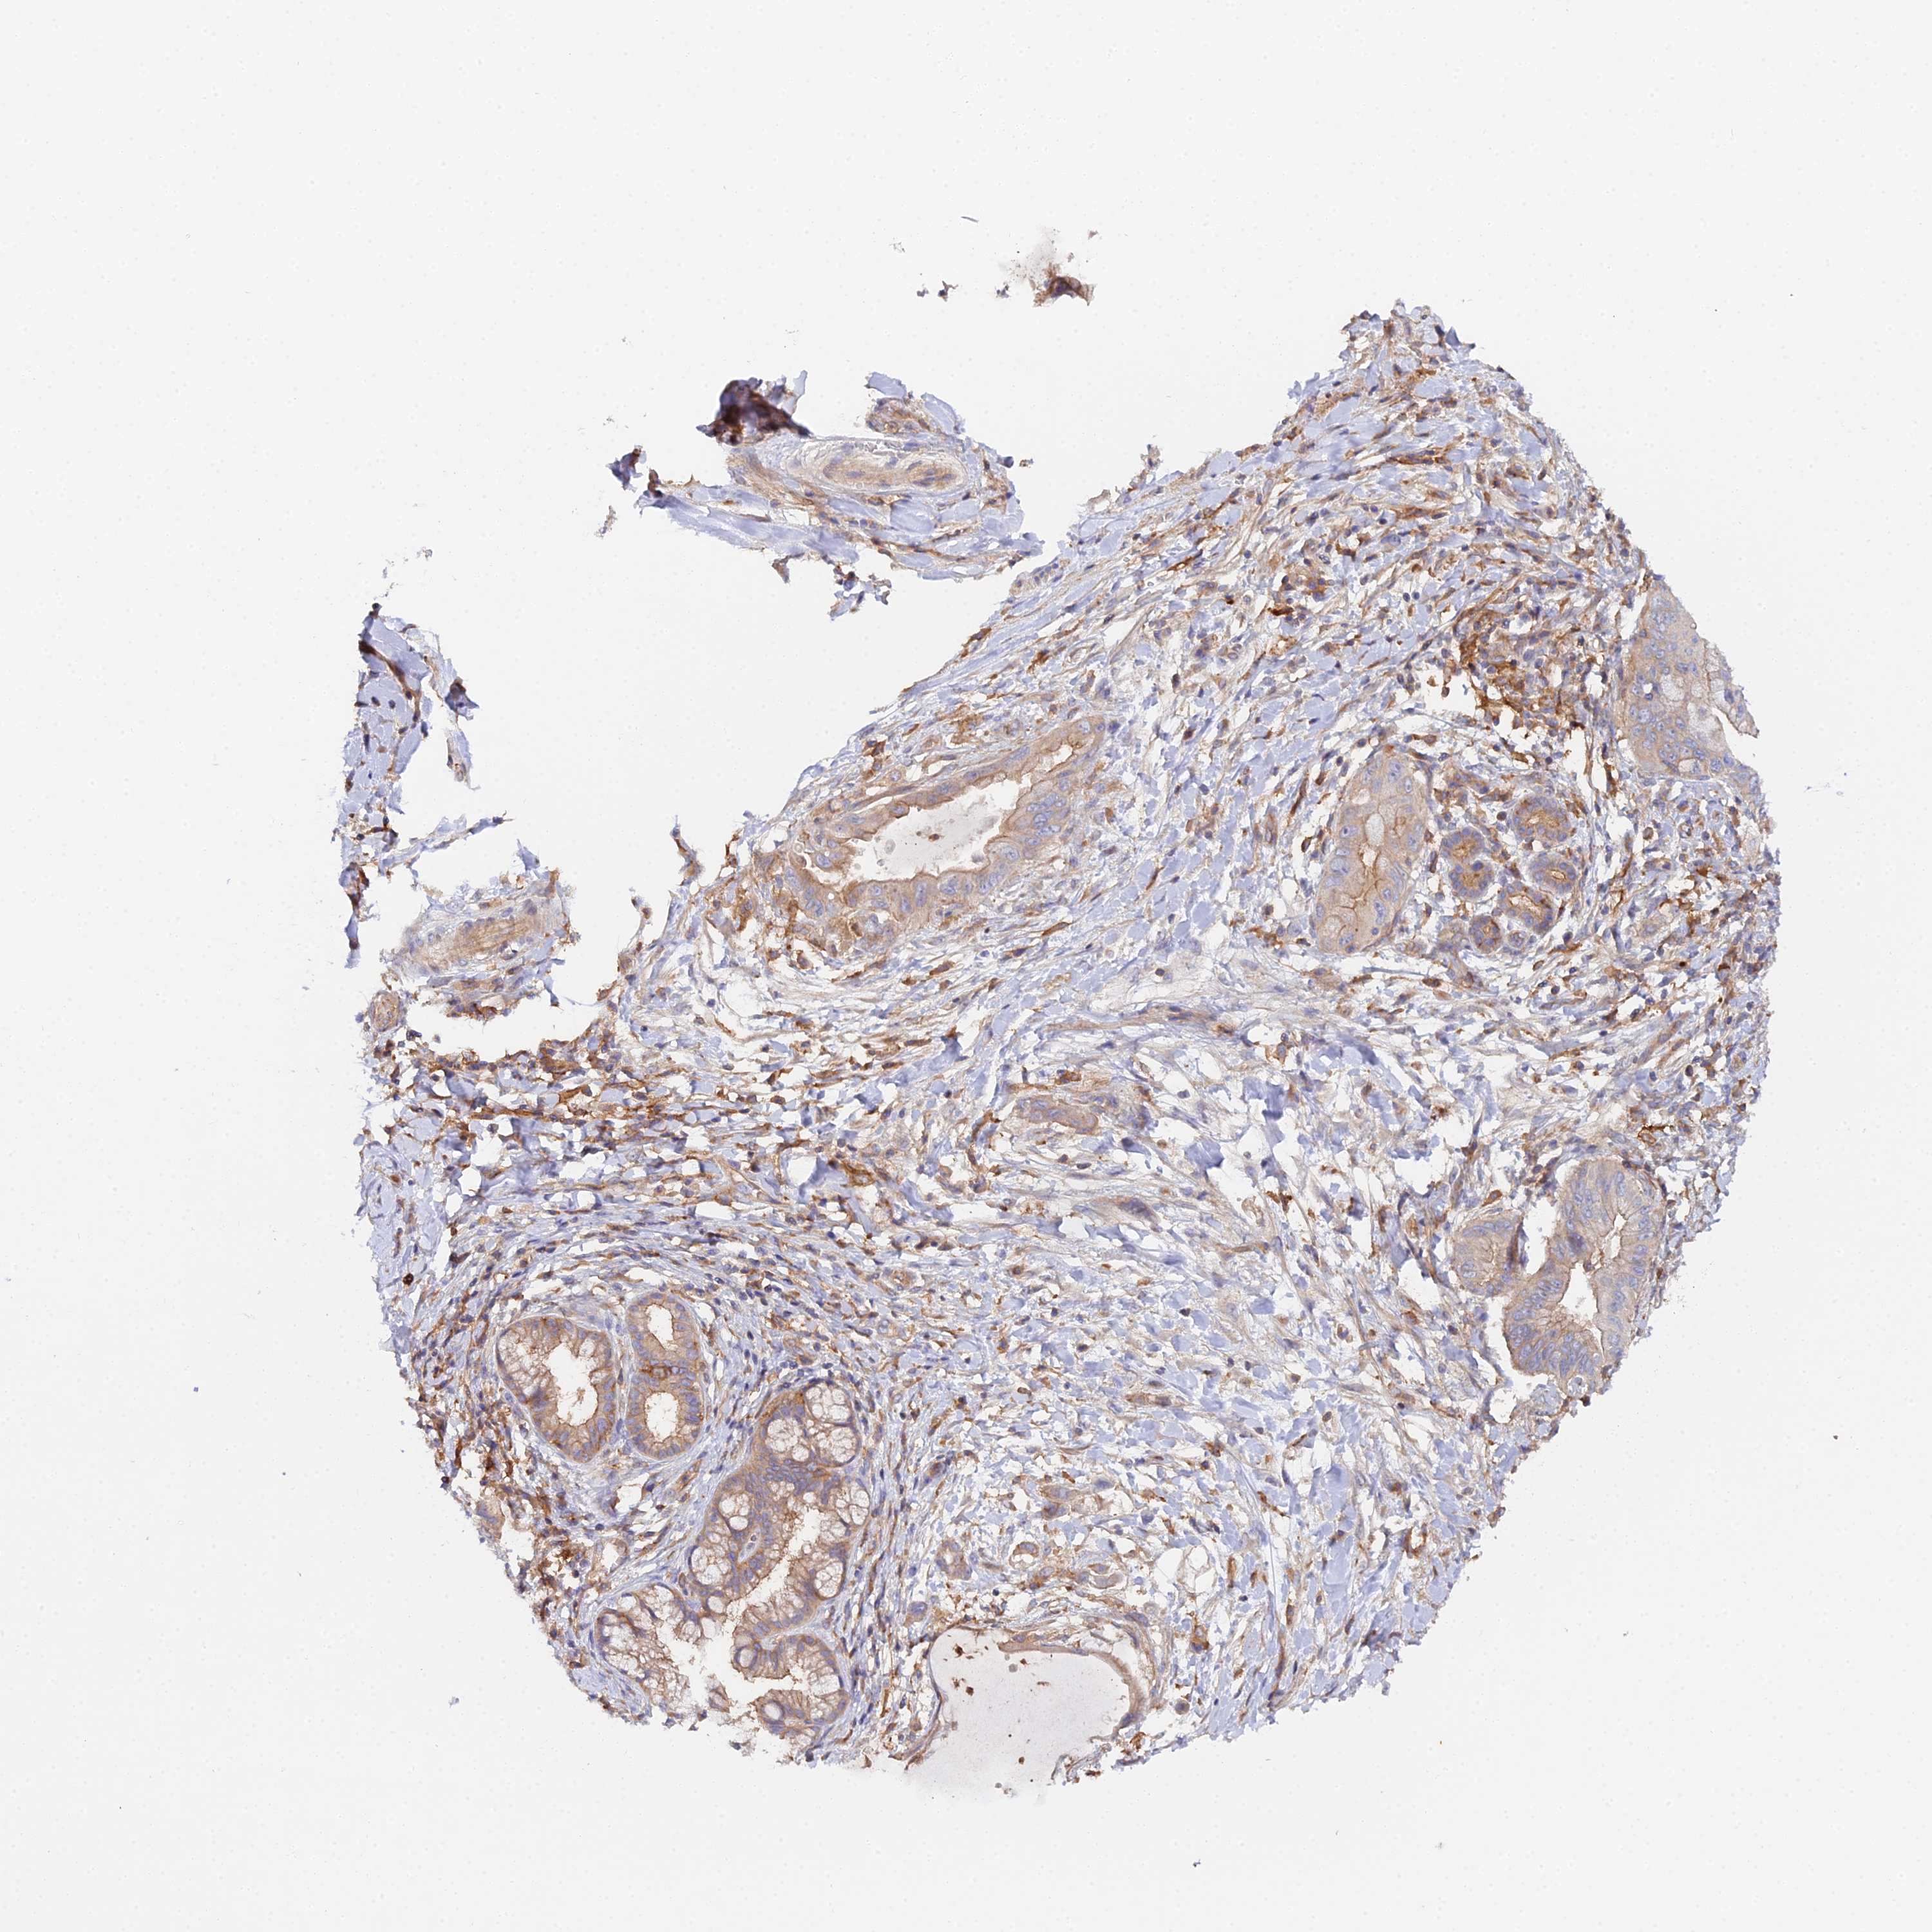

PANCREATIC CANCER - Protein expressioni

A mouse-over function shows sample information and annotation data. Click on an image to view it in a full screen mode. Samples can be filtered based on level of antibody staining by selecting one or several of the following categories: high, medium, low and not detected. The assay and annotation is described here.

Note that samples used for immunohistochemistry by the Human Protein Atlas do not correspond to samples in the TCGA dataset.

Antibody stainingi

Antibody staining in the annotated cell types in the current human tissue is reported as not detected, low, medium, or high, based on conventional immunohistochemistry profiling in selected tissues. This score is based on the combination of the staining intensity and fraction of stained cells.

Each image is clickable and will lead to virtual microscopy that enables deeper exploration of all samples and also displays staining intensity scores, fraction scores and subcellular localization as well as patient and tissue information for each sample.

Antibody HPA043651

Antibody CAB032623

Adenocarcinoma, NOS